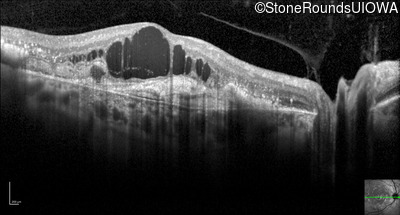

Optical Coherence Tomography - Right - 20/250

Exemplar / OCT Stack